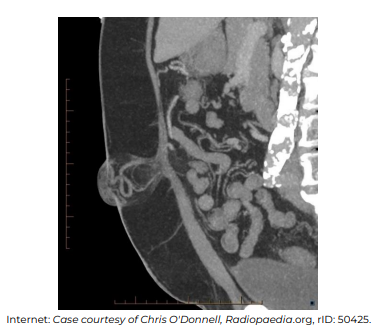

No que diz respeito à interpretação e ao diagnóstico nosológico que explica os achados na imagem apresentada, assinale a alternativa incorreta.